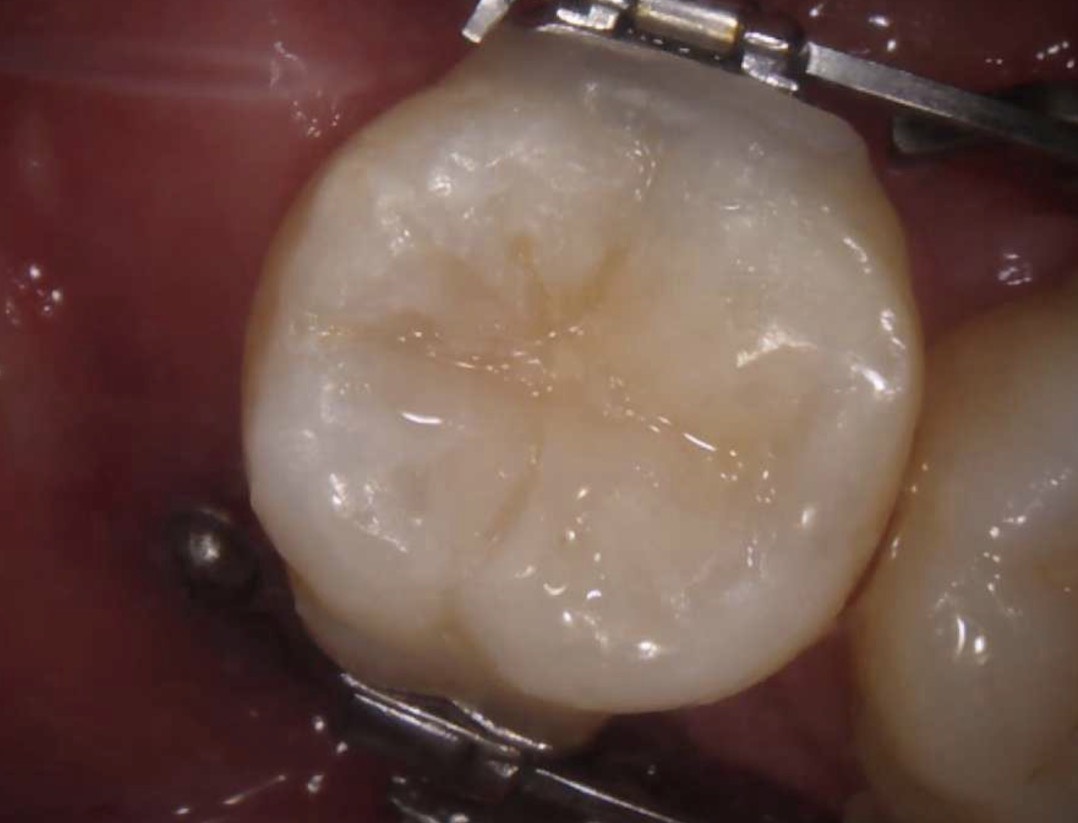

| 主訴 | 下の奥歯が黒くなっていて気になる |

|---|---|

| 所見 | 下顎右側第二大臼歯咬合面に充填物を認める。 |

| 診断 | 下顎右側第二大臼歯咬合面う蝕Ⅰ度 |

| 治療内容 | コンポジットレジン修復 |

| 治療後経過 | 痛みなく、咬合状態も良好。 |

| 治療期間 | 1回 |

| 治療費用 | 保険診療一本で1500円程度。 |

| リスク・副作用 | 今後も材料の経年劣化によって着色や不適合になる可能性があると伝えた。 |